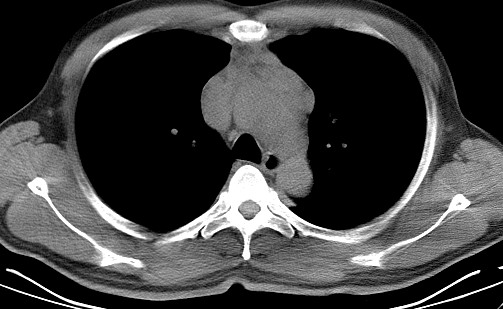

男   40   反复腹痛入院行彩超检查示胸骨右缘4、5肋间不均质回声团

淋巴瘤:前纵隔可见多组肿大的淋巴结,部分融合,有液化坏死

纵隔恶性肿瘤,考虑生殖细胞肿瘤可能性大。